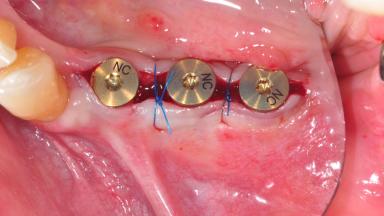

After the placement of three diameter-reduced two-piece implants the bone is augmented with autologous bone chips and DBBM particles to enlarge the crest volume. The surgery is completed with the application of two membrane layers and primary wound closure.